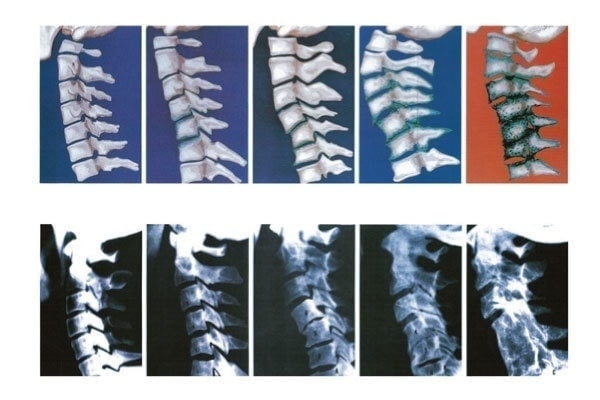

こちらの写真は頚椎の変性の具合を示していますが、椎間板周りの骨の状態が徐々に悪化しています。

なぜ、このように変性していくのか?

それは猫背やストレートネックなどのゆがみが生じていると頚椎ひとつひとつが正常に機能せず、動きの悪くなった関節は代謝が低下していくためです。

変性と呼ばれる現象は、誰しもが起こりうる変化ですが、骨格のゆがみは変性を助長してしまいます。

また、脊髄にまで影響が出る頚椎症性脊髄症は椎間板が原因で、骨に棘状の骨棘が発生し、靭帯が厚く硬くなって脊髄を押さえつけてしまいます。

方や、頚椎症性神経根症は頚椎の変性により、椎間孔に狭窄が発生することで、神経根が圧力を受け、痛みがでます。

このように、脊髄もしくは神経根の圧力のかかる部位により、頚椎症でも病名や症状が変化します。